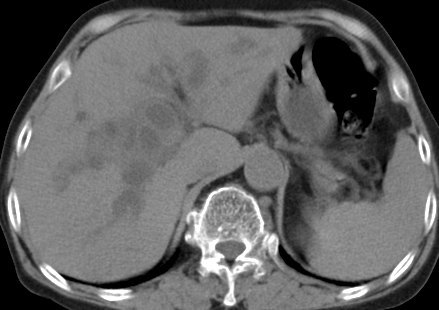

以下是引用齐原在2006-11-8 23:21:00的发言:[br]肝脏体积增大.肝表凸凹不平,肝内胆管扩张,胆总管扩张,胆总管末端突然截断,胰腺勾突增大,形态不规则.胰管扩张.考虑胰头癌.并低位梗阻性胆系扩张,胆囊炎.脾大.建议增强

以下是引用dyqct在2006-11-9 9:14:00的发言:[br]肝大,表面呈波浪状,肝内外胆管扩张,胆总管下端腔内见小结节状等密度影,胰管轻度扩张。胆囊显示不清。[br]考虑:1、胆总管下端占位性病变(等密度结石?壶腹部肿瘤?);[br] 2、肝硬化?[br] 3、建议增强扫描进一步检查。